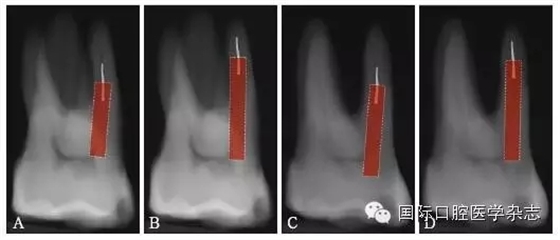

目前,對(duì)于分離器械周?chē)辣举|(zhì)厚度的評(píng)估以及取出后殘余牙本質(zhì)厚度的預(yù)測(cè)主要需借助影像學(xué)檢查,例如根尖片、錐形束CT(cone beamcomputed tomography,CBCT)圖像等。傳統(tǒng)的平行投照的根尖片無(wú)法反映三維立體結(jié)構(gòu),且往往存在解剖結(jié)構(gòu)影像的重疊,不利于臨床判斷,具有一定的局限性。多位學(xué)者[10]的研究表明:平行投照的根尖片會(huì)高估實(shí)際的牙本質(zhì)壁的厚度。一些學(xué)者[11-12]的研究表明:當(dāng)分離器械位于上頜第一磨牙近中根管時(shí),采用成角投照(21°)的拍攝技術(shù)與平行投照技術(shù)得到的X線(xiàn)片相比,能更準(zhǔn)確地評(píng)估牙本質(zhì)的厚度,為分離器械取出與否提供指導(dǎo)(圖4)。近年來(lái),CBCT在牙髓病學(xué)中的應(yīng)用越來(lái)越廣泛,由于CBCT能清楚地反映牙及牙根周?chē)M織的三維立體結(jié)構(gòu),為牙本質(zhì)厚度的評(píng)估與預(yù)測(cè)提供了可行性(圖5);因此,CBCT在器械分離的病例術(shù)前風(fēng)險(xiǎn)評(píng)估方面具有較好的應(yīng)用前景。

A、B:采用平行投照技術(shù)獲得的圖像,模擬取出分離器械后殘余牙本質(zhì)的厚度,分離器械分別位于根管口下3 mm和5 mm;C、D:采用成角投照技術(shù)獲得的圖像,模擬取出分離器械后殘余牙本質(zhì)的厚度,分離器械分別位于根管口下3 mm和5 mm。

圖 4 平行投照與成角投照拍攝技術(shù)對(duì)牙本質(zhì)厚度的評(píng)估